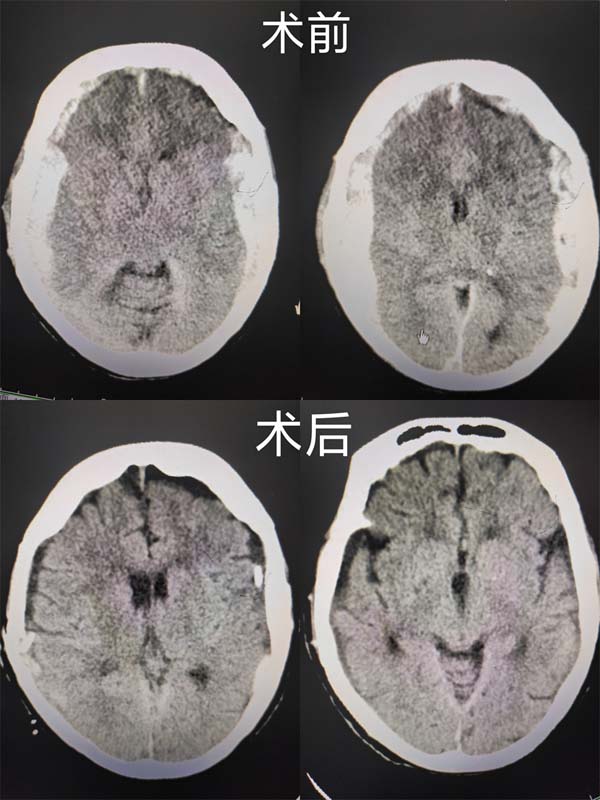

2022年1月1日(元旦)中午,随着120急救车的鸣笛声,应急总医院急诊科送来了一位93岁高龄头部摔伤,神志昏迷的老人,经急诊头颅CT检查,确诊:双侧额颞顶大面积颅内出血。

时间就是生命,神经外科秦怀海主任闻讯后立即赶到医院指挥安排手术方案,神经外科副主任靳文毅主任医师、沈寻副主任医师分别在接到通知20分钟内,从家里以最快速度赶到医院手术室,会同值班的朱晓慧医师一起为患者实施双侧开颅、颅内血肿清除手术,用时2小时40分钟,为患者清除双侧颅内硬膜下血肿近百毫升,手术室传出喜讯:手术取得圆满成功,患者重获新生。